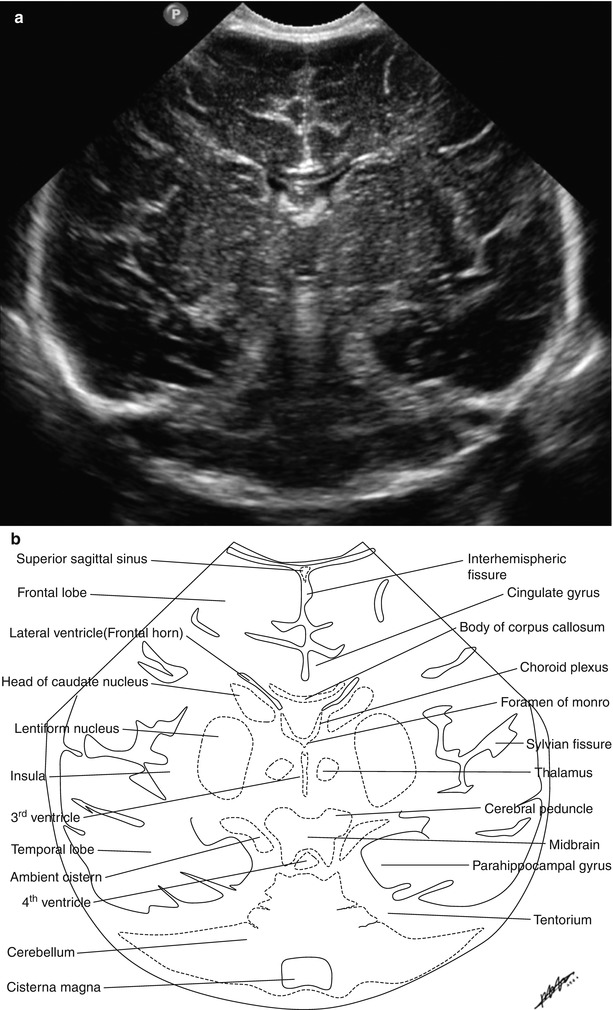

Normal Neonatal Brain Ultrasound Anatomy Caudothalamic Groove Ultrasound Subependymal cysts are most frequently seen in preterm infants, likely related to their persistent germinal matrix at the. Most infants are asymptomatic or demonstrate. These hemorrhages start in the caudothalamic groove and may extend into the lateral ventricle and periventricular brain parenchyma. Lamic groove or in the dependent portions of the occipital horns suggests germinal matrix and intraventricular hemorrhage, respec. Caudothalamic Groove Ultrasound.

Neurosonography Radiology Key Caudothalamic Groove Ultrasound Most infants are asymptomatic or demonstrate. Lamic groove or in the dependent portions of the occipital horns suggests germinal matrix and intraventricular hemorrhage, respec tively [4, 23]. These hemorrhages start in the caudothalamic groove and may extend into the lateral ventricle and periventricular brain parenchyma. In the us, grade 1 hemorrhage is seen as an echogenic mass in the. Subependymal. Caudothalamic Groove Ultrasound.